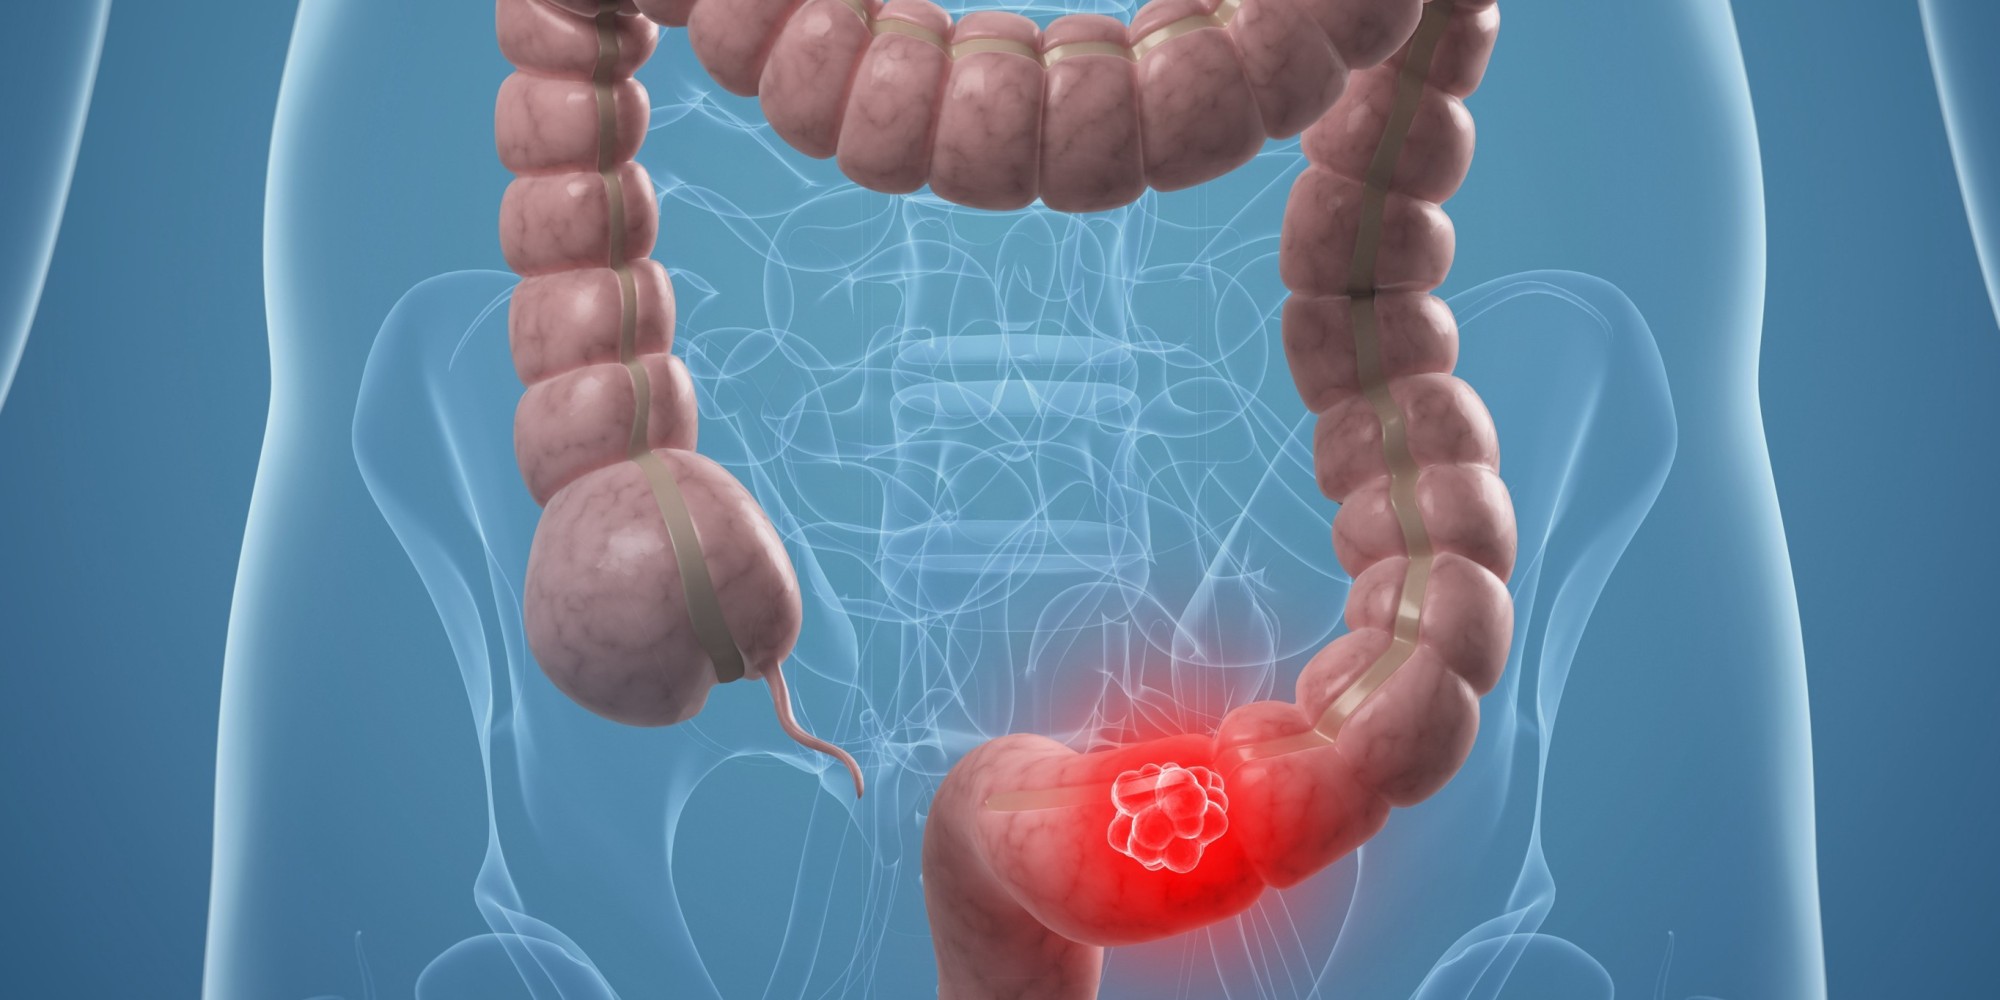

Οι πολύποδες του παχέος εντέρου βρίσκονται συχνά κατά τη διάρκεια μίας κολονοσκόπησης, όπου αφαιρούνται για να εξεταστούν κάτω από το μικροσκόπιο.

Οι πολύποδες είναι ένα επιπλέον κομμάτι ιστού που αναπτύσσεται μέσα στο σώμα σας. αναπτύσσονται στο παχύ έντερο ή στο ορθό. Οι περισσότεροι δεν είναι επικίνδυνοι. Ωστόσο, ορισμένοι μπορεί να μετατραπούν σε καρκίνο του παχέος εντέρου. Για την δική σας ασφάλεια, οι γιατρός θα αφαιρέσει τους πολύποδες και θα τους εξετάσει. Μπορούν να αφαιρεθούν και κατά τη διάρκεια μιας κολονοσκόπησης.

- Η εύρεση και η αφαίρεση τους μπορεί να βοηθήσει στην πρόληψη του καρκίνου του παχέος εντέρου ή του ορθού.